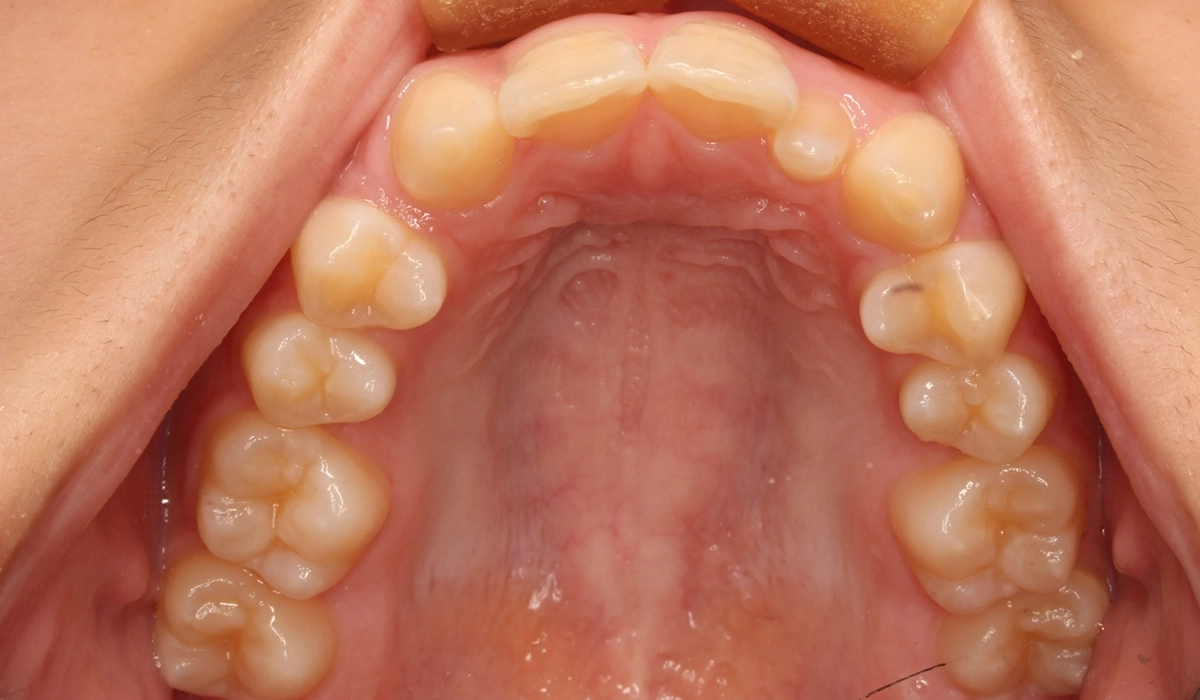

術前:上顎

術後:上顎

今回ご紹介する患者様は、上顎の歯並びのがたつきを気にされており、矯正検査後Ⅰ級叢生と診断いたしました。矮小歯があるため個性を生かして配列。

| 治療内容 | 上顎の歯並びのがたつきを気にされており、矯正検査後Ⅰ級叢生と診断。矮小歯があるため個性を生かして配列。 |